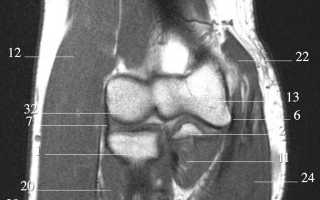

Интерпретация результатов магнитно-резонансной томографии (МРТ) локтевого сустава требует глубоких знаний анатомии, патологии и особенностей визуализации. МРТ является высокоинформативным методом, который позволяет детально оценить состояние мягких тканей, суставного хряща, связок, сухожилий и костей локтевого сустава.

При анализе результатов МРТ важно учитывать следующие ключевые аспекты:

- Анатомические структуры: Локтевой сустав состоит из трех основных костей: плечевой, локтевой и лучевой. МРТ позволяет визуализировать их взаимное расположение и состояние. Особое внимание следует уделить суставному хрящу, который может быть поврежден при травмах или дегенеративных заболеваниях.

- Мягкие ткани: МРТ дает возможность оценить состояние связок, таких как локтевая и радиальная связки, а также сухожилий, окружающих сустав. Патологии, такие как разрывы или воспаления, могут быть четко видны на изображениях.

- Синовиальная оболочка: Воспалительные процессы в синовиальной оболочке (синовит) могут быть выявлены с помощью МРТ. Увеличение объема синовиальной жидкости и утолщение оболочки являются признаками воспаления.

- Патологические изменения: На МРТ можно обнаружить различные патологии, такие как артрит, остеоартрит, бурсит и другие. Важно правильно интерпретировать изменения в тканях, чтобы установить точный диагноз.

- Контрастирование: В некоторых случаях для улучшения визуализации может использоваться контрастное вещество. Это позволяет более четко увидеть воспалительные процессы и опухолевые образования.